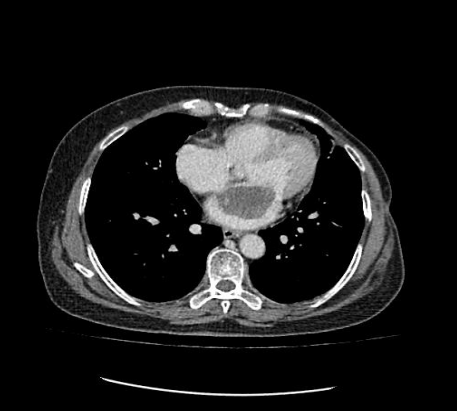

患者為一名57歲的女性,心慌、胸悶的癥狀已有一年多,一直以為是“感冒”而沒放在心上。最近經人介紹到我院檢查,經心臟超聲檢查發(fā)現(xiàn)左心房上長了一個雞蛋大小的黏液瘤。雖說是良性的,但生長位置在二尖瓣口,如果黏液瘤碎片或瘤體表面血栓脫落,可發(fā)生體循環(huán)或肺循環(huán)的栓塞,隨時有猝死的危險。以往此類疾病必須通過傳統(tǒng)胸部正中切口實施手術,病人術后要經過3-6個月左右的恢復期,患者創(chuàng)傷大、恢復慢、出血較多、切口瘢痕明顯、心理負擔重,無論是對身體還是心理都是一次嚴重創(chuàng)傷。為患者實施全胸腔鏡技術摘除左心房黏液瘤手術,在不破壞患者破壞胸骨穩(wěn)定性的前提下,只需在患者胸壁上開2個“鑰匙孔”樣大小觀察孔和1個4cm的操作孔即可進行手術,最大限度減少術后疼痛和創(chuàng)傷,縮短術后恢復時間。

據(jù)悉,胸腔鏡微創(chuàng)心臟手術是目前世界上頂級的微創(chuàng)心臟手術,對外科醫(yī)生的經驗和技術要求高。適合的病種包括二尖瓣病變、三尖瓣病變、房間隔缺損、室間隔缺損、左心房或右心房腫瘤等,尤其對左心瓣膜術后發(fā)生的三尖瓣重度關閉不全需要再次手術的患者具有極為突出的優(yōu)勢。